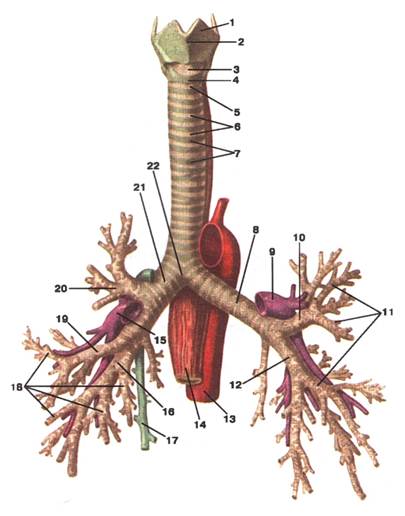

Малюнок А. 3 – Trachea et bronhi. Вигляд спереду:

1 -cartilago thyroidea; 2 -prominentia laryngea; 3 -lig. cricothyroideum; 4 -cartilago cricoidea; 5 -lig. cricotracheale: 6 -ligg. anularia; 7 -cartilagines tracheales; 8 -bronchus principalis sinister: 9 -а. pulmonalis sinistra; 10 -bronchus lobaris superior sinister; 11 -bronhi segmentales; 12 -bronchus lobaris inferior sinister; 13 -aorta; 14 -oesophagus; 15 -a. pulmonalis dextra; 16 -bronchus lobaris inferior dexter; 17 -v. azygos; 18 -bronchi segmentales; 19 -bronchus lobaris medius dexter; 20 -bronchus lobaris superior dexter; 21 -bronchus principalis dexter; 22 -bifurcatio tracheae